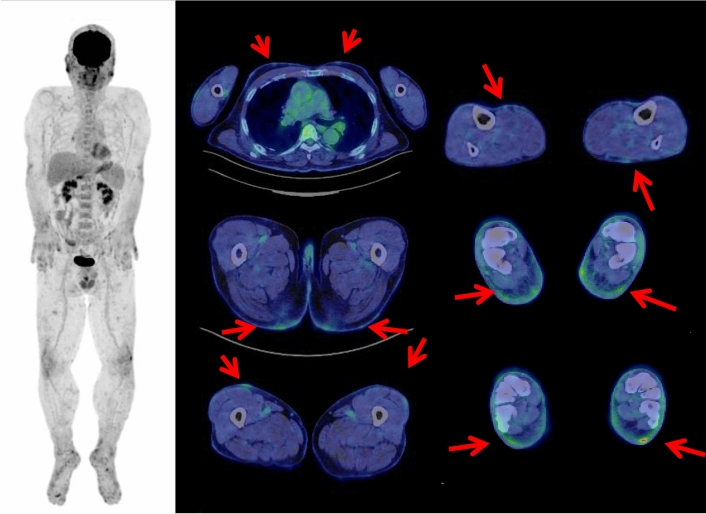

Only a few studies and case reports evaluate the potential role of FDG PET/CT in diagnosing primary cutaneous lymphomas [52–57]. Several studies indicate that FDG PET/CT is more accurate than CT in detecting both cutaneous and extra-cutaneous diseases of T cell lymphomas including mycosis fungoides [52–54]. We have experienced a total of 8 patients with primary cutaneous lymphomas (including 2 patients of mycosis fungoides), all of which showed FDG-avid cutaneous lesions (Fig. 8).

Fig. 8.

A 64-year-old male suffered rash-like skin redness, slightly raised or scaly round patches on the skin of the face, trunk and extremities. The biopsy of the skin lesion revealed the diagnosis of cutaneous peripheral T cell lymphoma. Whole-body FDG PET maximum projection and cross-sectional images showed FDG uptake (SUVmax 4.5) in the systemic skin lesions (arrows)